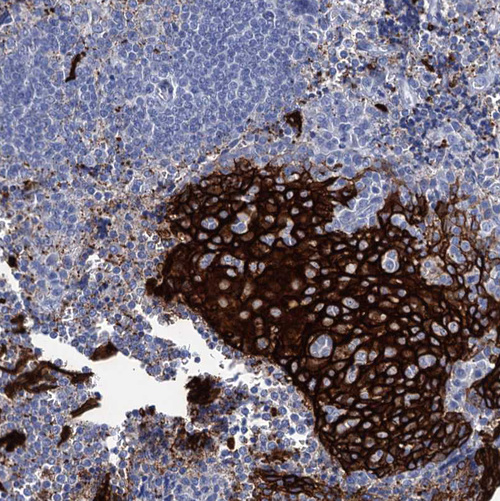

Immunohistochemistry analysis in human esophagus and pancreas tissues using HPA041874 antibody. Corresponding RHCG RNA-seq data are presented for the same tissues.